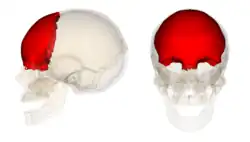

O crânio humano pode ser dividido em duas partes: o neurocrânio, que forma uma caixa protetora do cérebro, e o esqueleto facial ou esplancnocrânio.[2] O neurocrânio corresponde à parte superior e posterior do crânio que apoia as estruturas da face e protege o cérebro. É constituído principalmente por ossos e placas de cartilagem achatadas, formando uma cavidade onde ficam alojados o cérebro e vários órgãos dos sentidos - a visão, o olfato e o ouvido. Do neurocrânio fazem parte a calota craniana (ou calvária) e a base do crânio.[3]

Osso parietal (par)

Osso parietal (par)